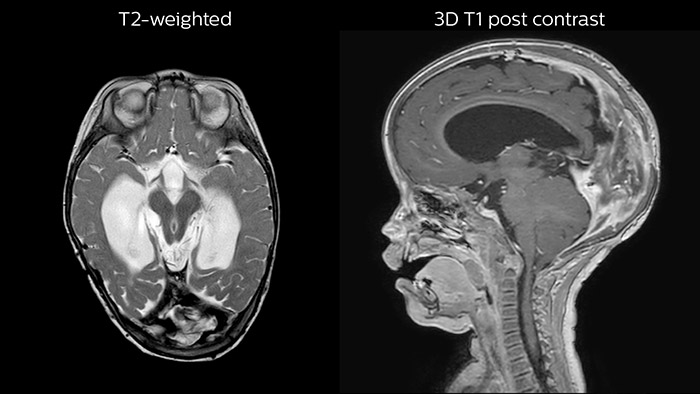

Dural sinus malformation (DSM) Initial examination

After three times of coiling and acryl based embolization

Hydrocephalus post hemorrhagic Both pictures show a ventriculoperitoneal shunt. With our previous scanner our hydrocephalus protocol needed about 25 min. With Ambition the examination time is about 14 min. including a CSF PCA sequence to show flow in the aqueduct.

Rostral meningitis and arachnoiditis Both images are from the same 3D T1-weighted post contrast sequence in a newborn, under treatment.